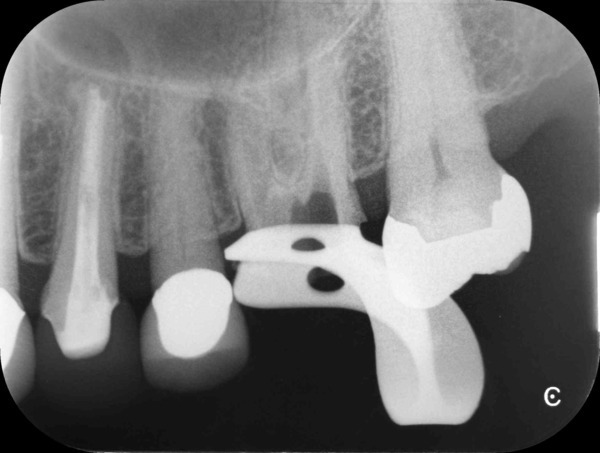

術前のデンタルX線写真と口腔内写真です。左下の一番奥の歯(#37)です。

左下の親知らずは1ヵ月ほど前に抜いたそうです。

親知らずと隣り合っていた歯の後ろ側(遠心)から虫歯が進行しています。